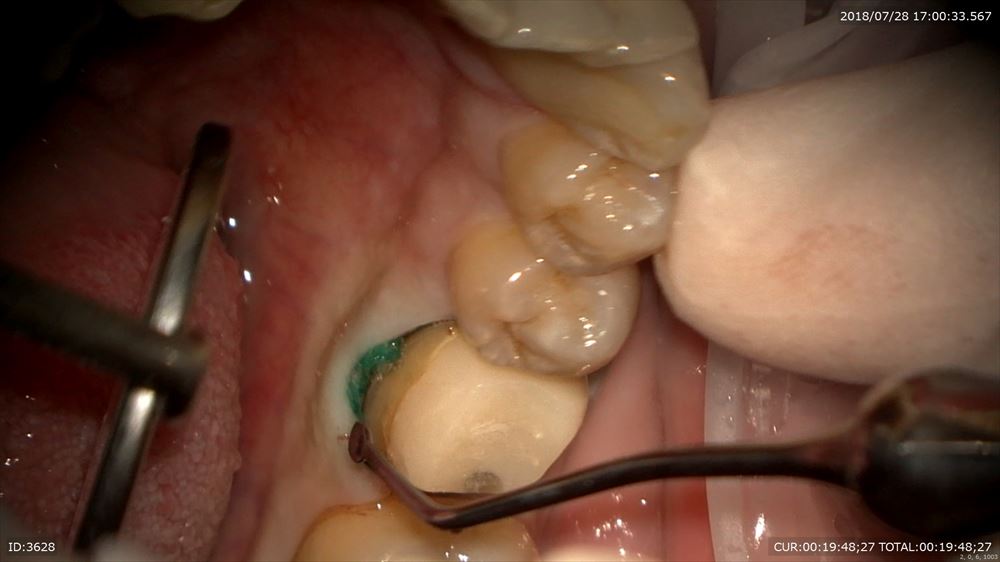

糸を入れるのは隙間を作るから。この緑を外すと

ここ。隙間ができここに型取りの材料を流します。

精密根管治療の予後は精密な型とりと精密な被せ物が重要だと報告があるようにこのステージが大切。